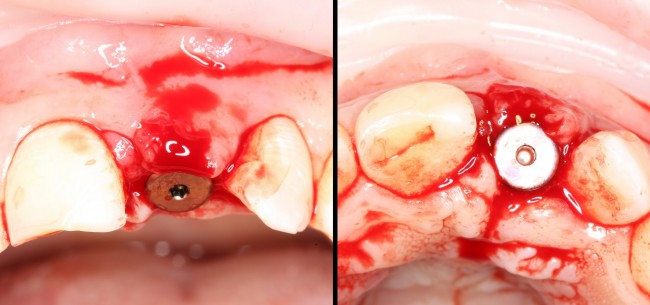

Продолжим нашу работу. Имплантат установлен:

Работа закончена? Отнюдь, нет. Теперь наша задача — восстановить утраченные объемы костной ткани вокруг импланта. Ибо, как вы видите на фото, его вестибулярная поверхность, практически, просвечивает. И, если ничего не делать, дальше будет только хуже.

Итого, наиболее оптимальным в данной ситуации оказалась направленная тканевая регенерация с использованием барьерных мембран. В качестве барьерной мембраны у нас будет Geistlich BioGide. Ее очень легко адаптировать и позиционировать:

Начну с того, что BioGide — это лучшее, что есть сейчас на рынке, а остальные мембраны ей завидуют. Как и в случае с макродизайном имплантов, именно физические свойства определяют как удобство использования, так и возможность достижения нужного результата. Прочность, эластичность, легкая адаптация и адгезия делают ненужными использование фиксирующих пинов. Мы просто закрываем мембраной графт — и все, можно накладывать швы:

В другом ракурсе видно, какой объем тканей мы восстанавливаем:

и теперь швы. Наглухо (Фактор II):